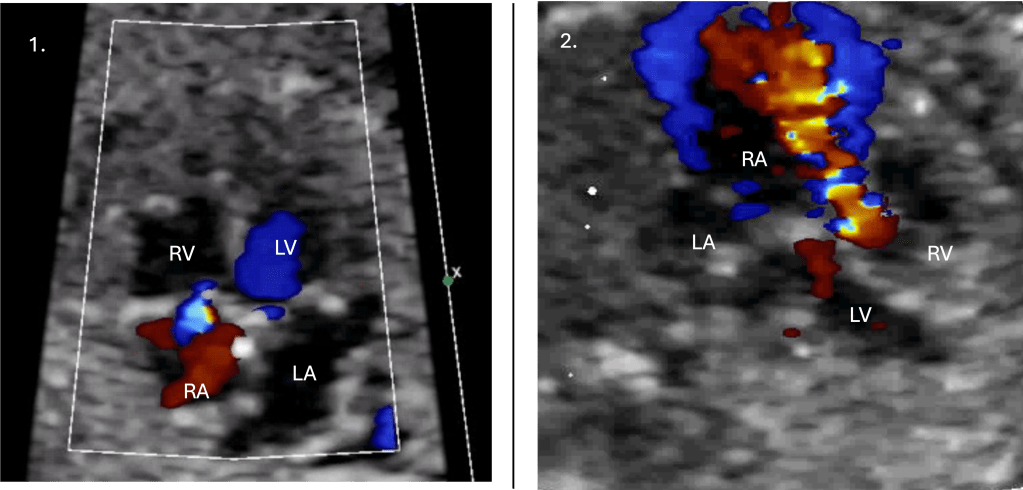

7. Tricuspid regurgitation on fetal echocardiography

At this stage, the Fetal cardiologist evaluates:

- TR characteristics (timing, velocity, jet morphology)

- Valve appearance

- Hemodynamic context (chamber size, cardiomegaly, venous Dopplers)

Earlier studies have used lower velocity thresholds (e.g.,>2.0 m/s) to define non-trivial tricuspid regurgitation; in contemporary practice, a higher threshold (≈2.5 m/s) is more useful for distinguishing physiological jets from those that may reflect increased right ventricular pressure.